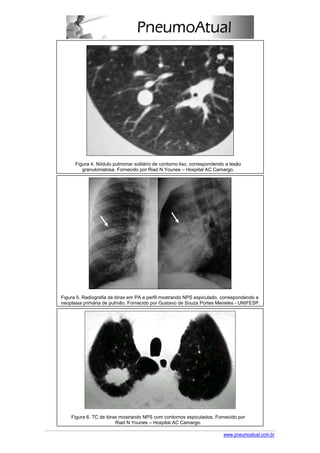

Bordas regulares ou lobuladas são mais comuns em lesões benignas (figuras 3 e 4), enquanto

bordas irregulares e espiculadas sugerem lesões malignas (figura 5 e 6). Estas características

não são absolutas e 10% a 20% dos NPS malignos têm bordas lisas.

Figura 4. Nódulo pulmonar solitário de contorno liso, correspondendo a lesão

granulomatosa. Fornecido por Riad N Younes – Hospital AC Camargo.

Figura 5. Radiografia de tórax em PA e perfil mostrando NPS espiculado, correspondendo a

neoplasia primária de pulmão. Fornecido por Gustavo de Souza Portes Meireles - UNIFESP.

Figura 6. TC de tórax mostrando NPS com contornos espiculados. Fornecido por

Riad N Younes – Hospital AC Camargo.